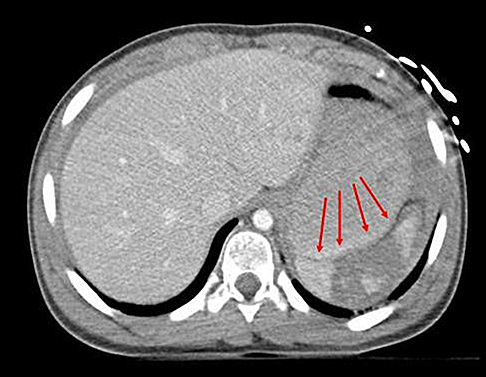

year-old boy who was found unresponsive after a diving accident. He had to be extricated from the bottom of a swimming pool by friends and was intubated at the scene by paramedics. In the emergency department, he was found to have weak triceps and grip strength bilaterally. Lower extremity strength was trace (grade 1 of 5). Sensation was diminished below the T2 dermatome. He had an absent bulbocavernosus reflex. Immediate open posterior reduction and stabilization were performed. Postoperative MRI revealed no iatrogenic disk herniation. Postoperative neurologic function revealed grade 4 strength in the triceps, wrist flexors, and bilateral grip. His lower extremity strength was grade 3. The sensory examination showed only slight diminution in the legs bilaterally. His bulbocavernosus reflex returned on postoperative day 2. On postoperative day 3, he required reintubation and was noted to require high positive end-expiratory pressures and a high ventilatory rate to keep him oxygenated. On postoperative day 4, his temperature was 38.7° C, blood pressure was 90/48, and pulse was 110 beats per minute. The urinary output measured 32 ml per hour. The white blood cell count was 14.8 with a left shift. A chest CT was ordered, and the results are shown in Figure 3. What best describes his condition?

4. Septic shock Discussion: D

Aspiration pneumonia developed, as seen on CT, and presumably occurred during his near drowning accident. His laboratory values and hemodynamic status are characteristic for septic shock. His original neurologic injury is an incomplete spinal cord injury, but after reduction and stabilization, he showed neurologic improvement, so this injury should not have contributed to his circulatory problems. The treatment for septic shock is broad spectrum antibiotics (species specific if the pathogen is identified) and pressors.